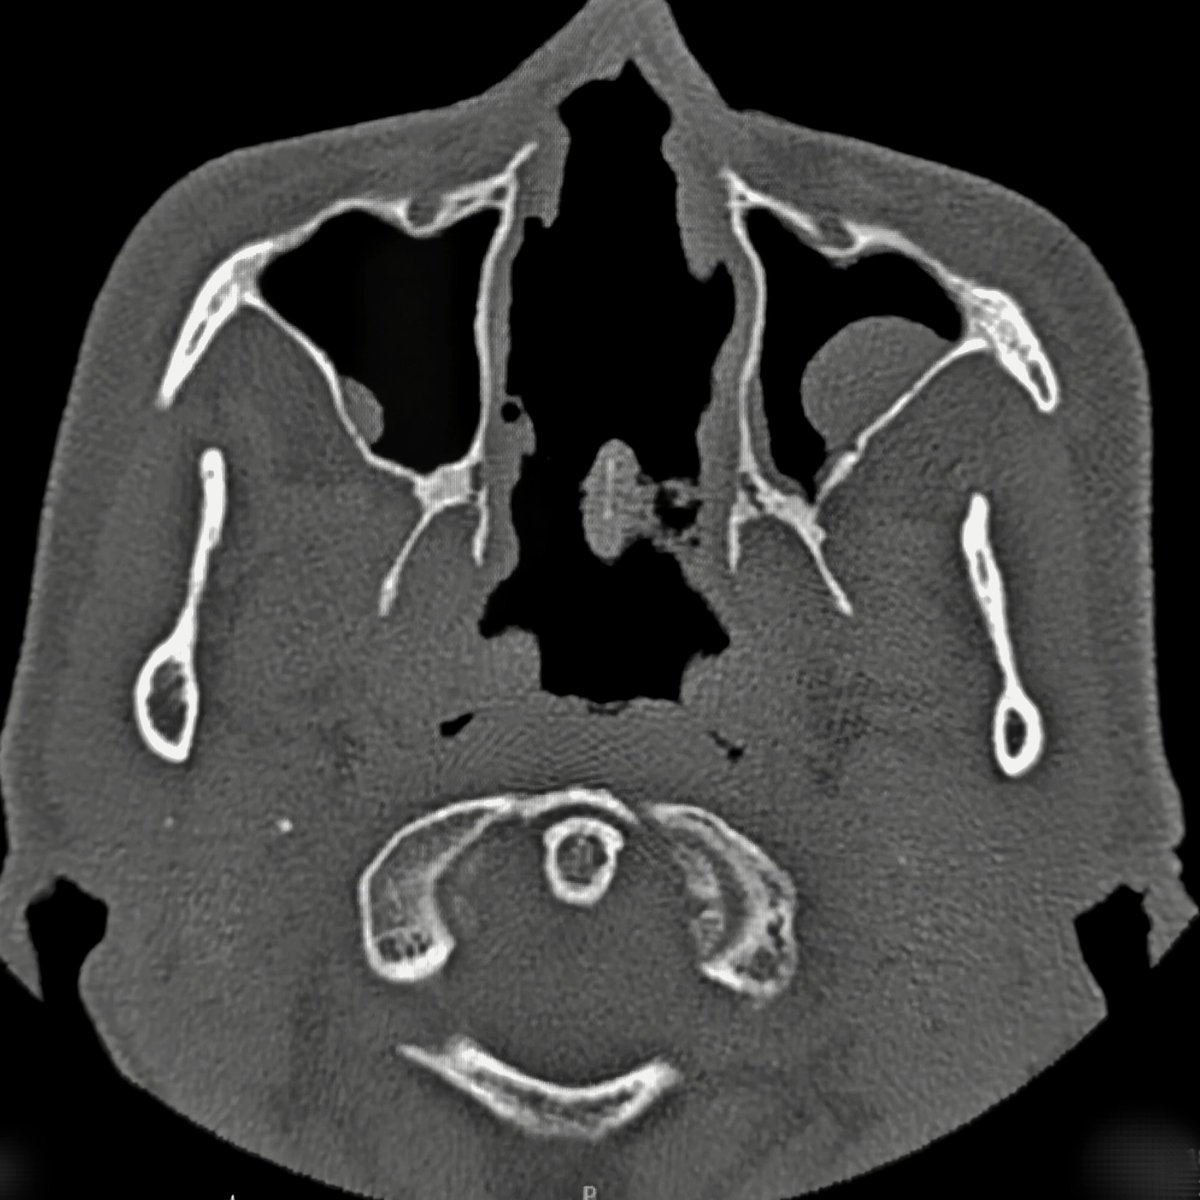

наркотики - зло! 💁 ж49, носовую перегородку и раковины пожрал кокс 😒

ж49, носовую перегородку и раковины пожрал кокс 😒